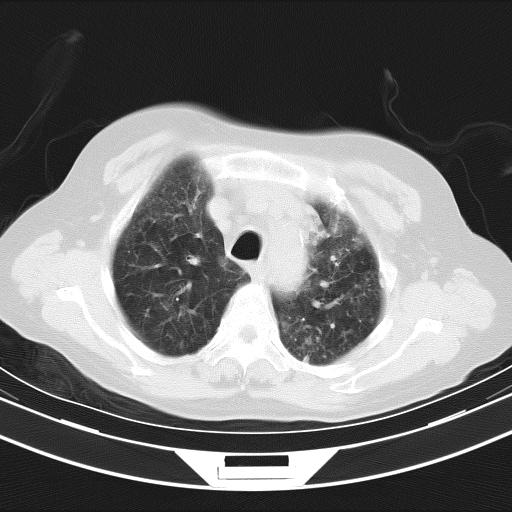

老年女性,嗜睡3天,意识模糊。轻咳,无发热。

两肺慢支炎伴感染,左侧胸腔积液。纵膈及双侧肺门淋巴结肿大建议复查。

双肺多发淡片影,毛玻璃影,,支持支气管肺炎,,建议血气找原因,,嗜睡是否肺性脑病?有没有慢支病史?

双肺炎症,建议抗炎治疗后复查,见过几个老年肺炎病例,没有发烧、咳嗽症状,直接以昏迷就诊。

1)两肺感染性病变;建议抗炎治疗后复查。2)纵隔淋巴结肿大。3)左侧胸腔积液。